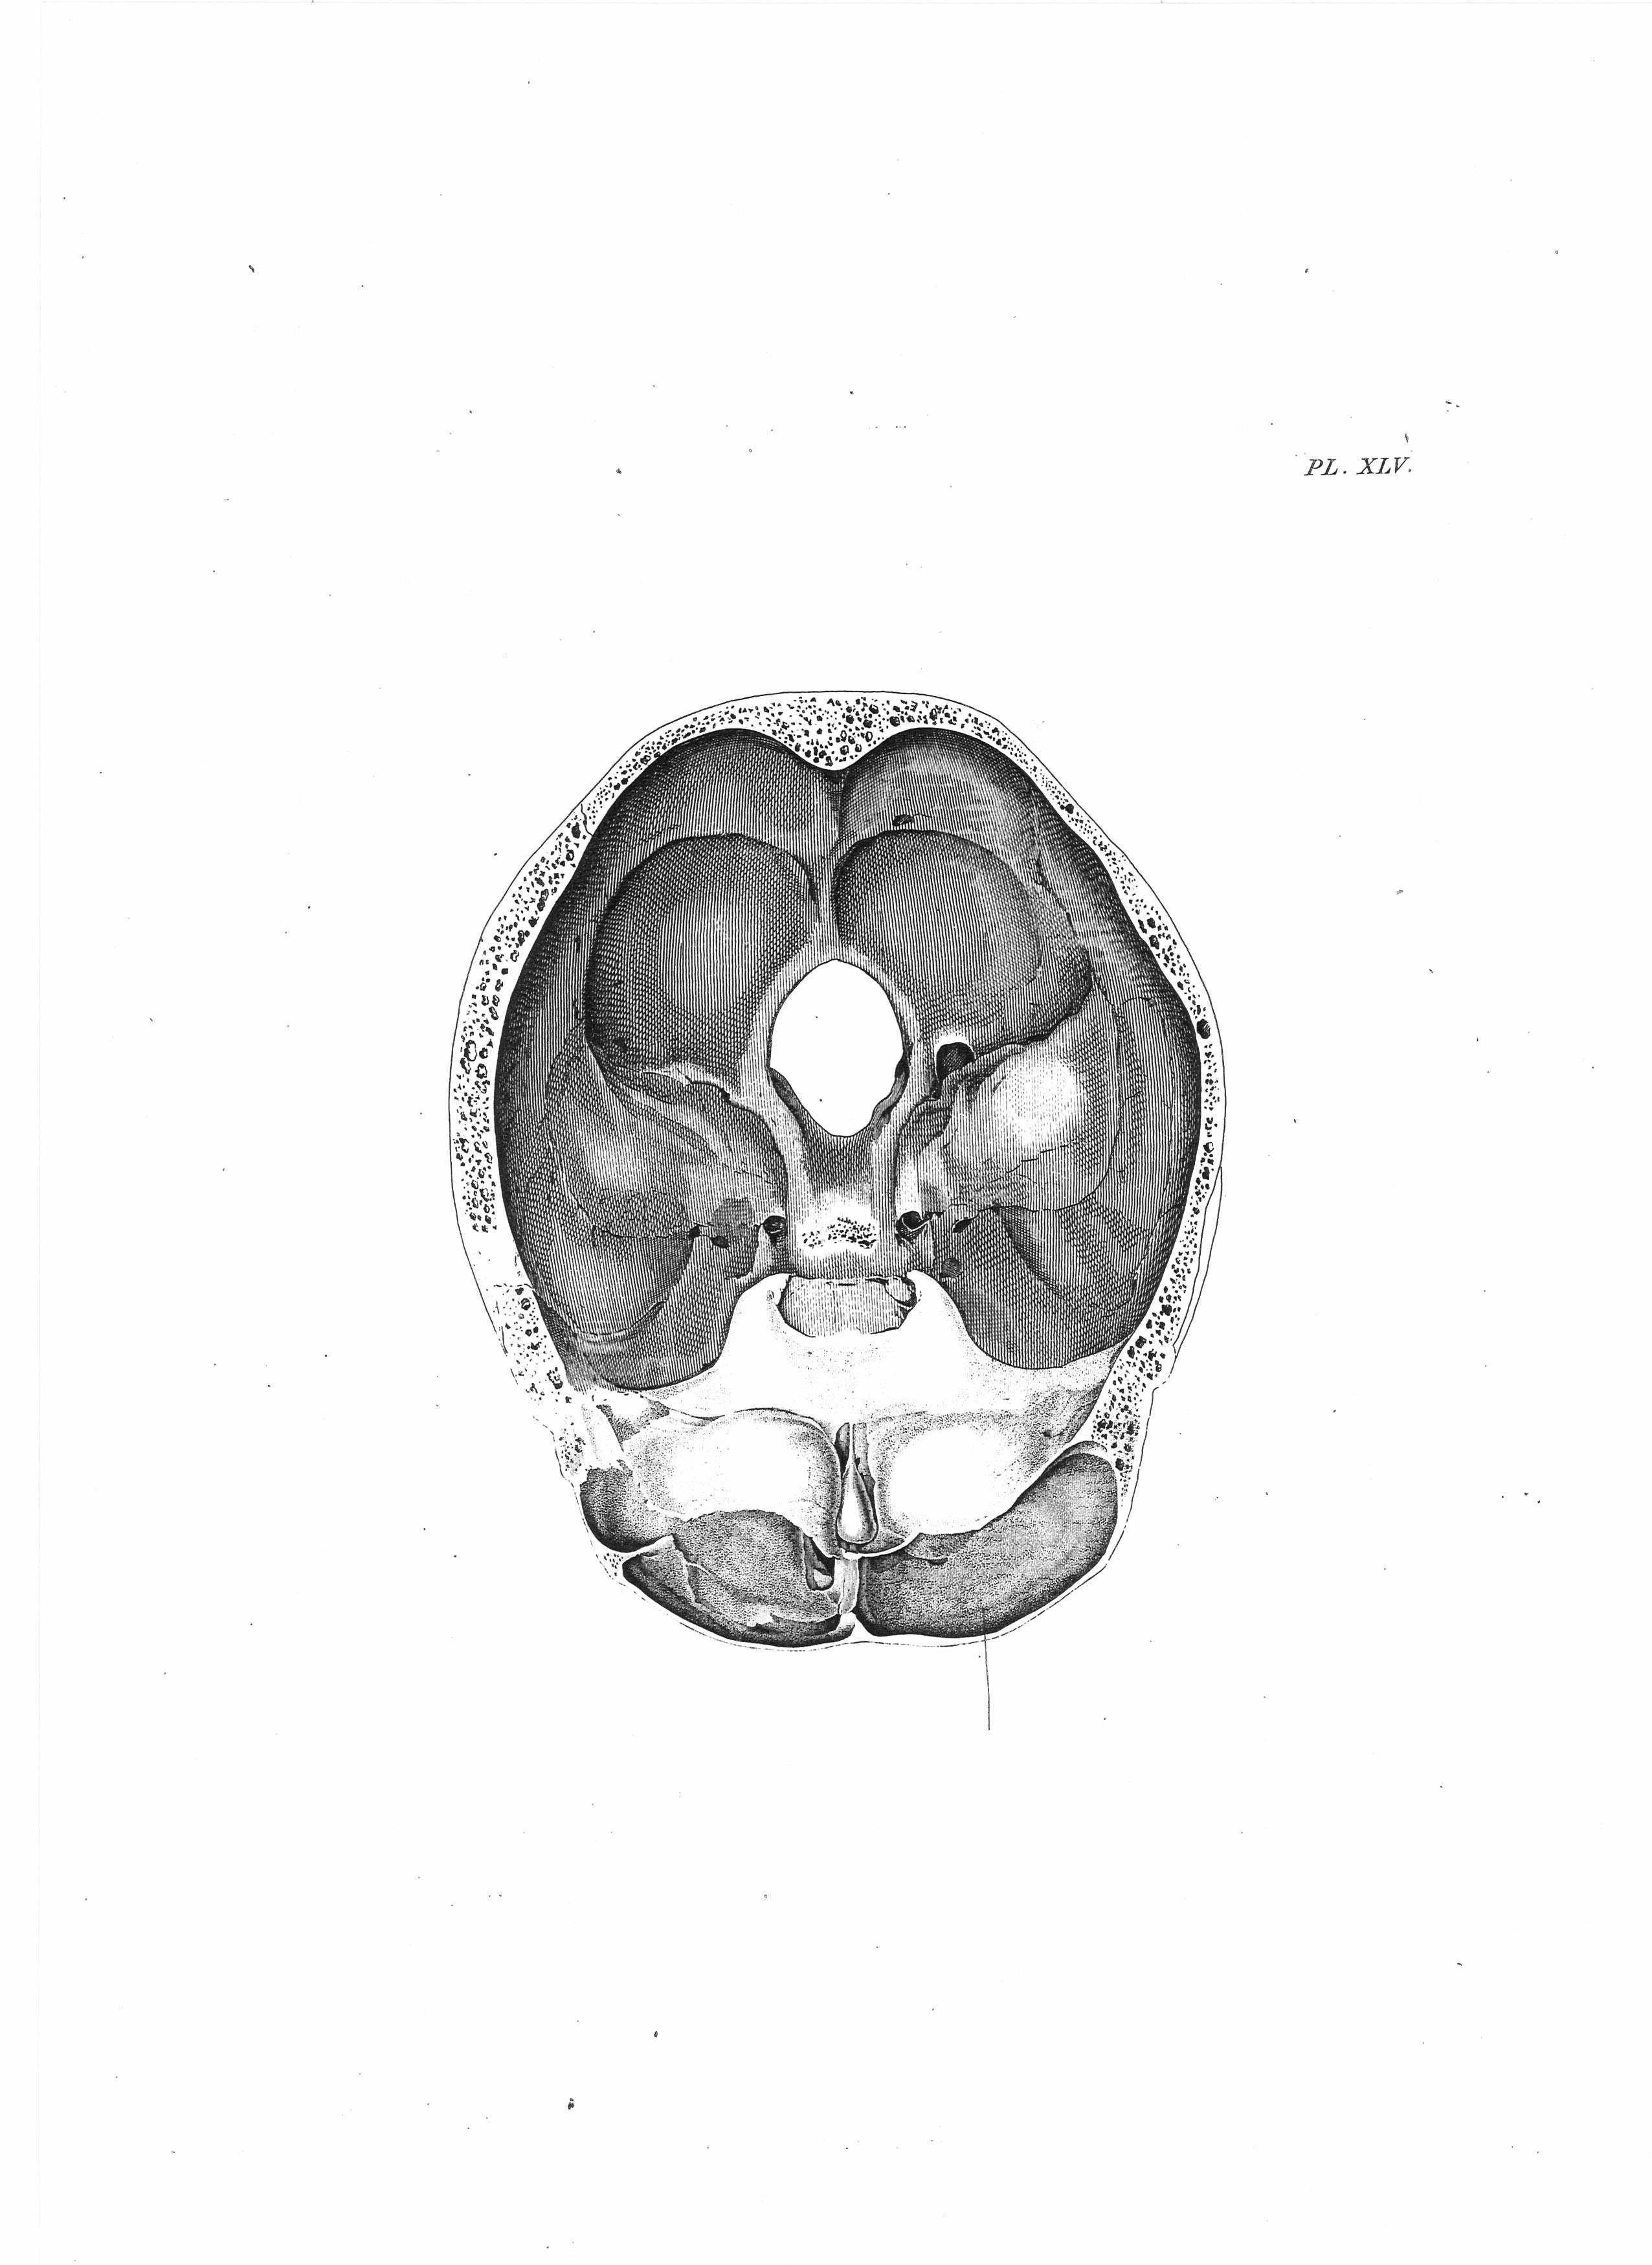

Gall, F. J. (1818). Anatomie et physiologie du système nerveux en général, et du cerveau en particulier, Avec des observations sur la possibilité de reconnoître plusieurs dispositions intellectuelles et morales de l´homme et des animaux, par la configuration de leurs têtes.

Librairie Grecque-Latine-Allemande, Vol. 3, I-XXXV u. 1-379 100 planches.